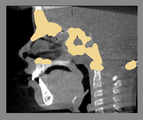

For assessment of overall facial changes, cranial base segmented models are only used to mask anatomic structures that change with growth and treatment. The registration procedures actually compare voxel by voxel of gray-level CBCT images, containing only the cranial base, to calculate rotation and translation parameters between the 2 images. Cranial base registration yields information of facial displacements relative to the cranial base. For subjects in whom cranial base growth is complete, registration is done using the gray level CBCT datasets of the whole cranial base ( Nongrowing registration module). The larger the number of voxels used for the registration, the more robust the registration is. For this reason, for adult patients the whole cranial base “mask CBCT” is used for registration. For growing patients ( Growing registration module), the registration includes two steps in the same module: in the first, an initial head alignment is done using the whole cranial base, and then a finer registration is performed at the stable structure on the anterior cranial base. For assessment of localized facial changes, such as mandibular or maxillary growth or bone remodeling of the mandibular condyle or tooth movement, specific anatomic regions can be used to create localized masks and aid regional superimpositions. The challenge in regional superimpositions is to determine which structures offer stable reference for registration.

- Mask creation: segmentation files are used to : 1: generate CBCT files that can be used to mask anatomic regions that changed with growth and treatment ; or 2: generate a CBCT file that contains only the anatomic region of interest for regional superimpositions.